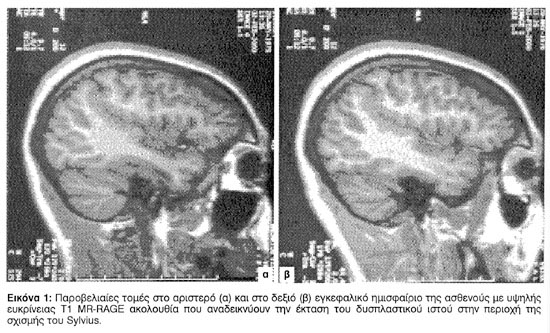

Ο έλεγχος με μαγνητική τομογραφία υψηλής ευκρίνειας (Εικ. 1) ανέδειξε εκτεταμένη φλοιική δυσπλασία, η οποία εκτεινόταν από την αριστερή σιλούειο αύλακα έως την οπίσθια κεντρική σχισμή. Στις περιοχές αυτές ο φλοιός ήταν πεπαχυμένος και το μεταίχμιο λευκής-φαιάς ουσίας παρουσιάζονταν ασαφές. Παρόμοιες αλλοιώσεις υπήρχαν και πέριξ της δεξιάς σιλούειας σχισμής. Ο λεπτομερής έλεγχος των ιπποκάμπων δεν αποκάλυψε ασυμμετρίες ή διαταραχές της εσωτερικής δομής ή του σήματος αυτών.